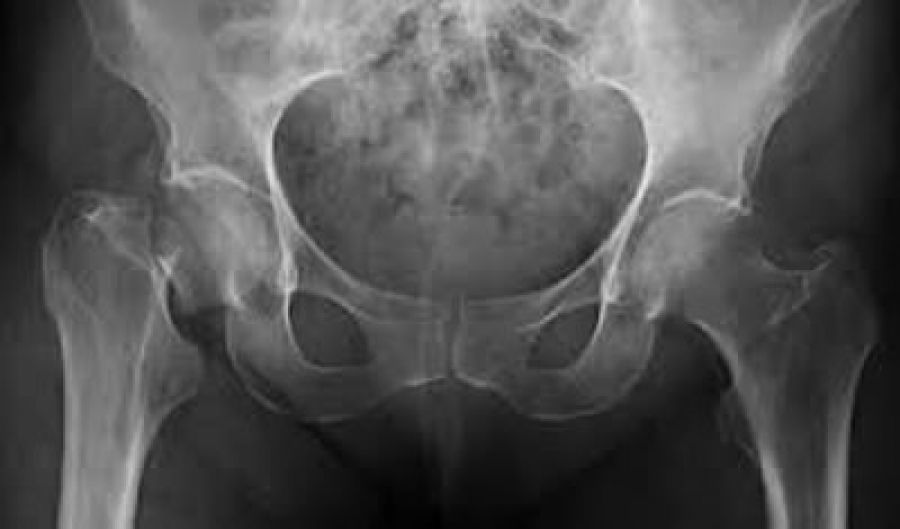

La osteoporosis es conocida como “la epidemia silenciosa”, ya que no tiene síntomas y cada vez afecta a más personas. Se estima que en el mundo se produce una fractura por osteoporosis cada tres segundos3, además, teniendo en cuenta que esta enfermedad causa más de 8.9 millones de fracturas anuales(1) y que en México 3.5 millones de personas mayores de 60 años requieren tratamiento o prevención para este padecimiento(2) se considera ésta una iniciativa necesaria.

Asimismo, se debe tener en cuenta que los antecedentes de haber sufrido una fractura por fragilidad predisponen al paciente a un riesgo considerable de sufrir fracturas futuras; lo que ilustra la gran necesidad de implementar estrategias de prevención para fracturas secundarias.

Actualmente, existen terapias que ayudan a controlar la pérdida ósea y refuerzan los huesos para evitar posibles fracturas, sin embargo no existe una cura para la osteoporosis. Existen diversas opciones de tratamiento como tabletas, parches o inyecciones (4, 5, 6). Amgen ha desarrollado Denosumab, una terapia biotecnológica que se inyecta de manera subcutánea dos veces al año, lo que permite un mayor apego al tratamiento, que ayuda a incrementar la densidad mineral ósea y reducir la incidencia de fracturas de cadera, vertebrales y no vertebrales.